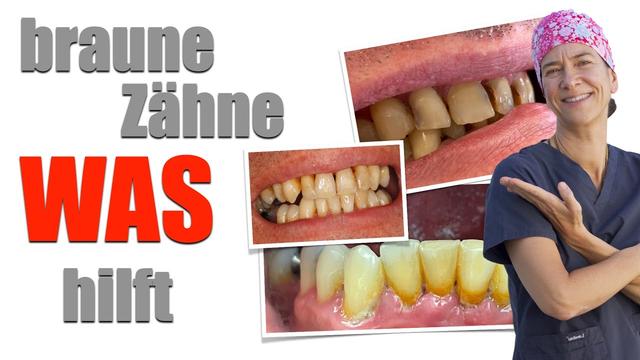

Möchten Sie braune Flecken auf Ihren Zähnen selbst entfernen? In diesem Artikel finden Sie einfache und effektive Methoden, um Ihre Zähne wieder strahlend weiß zu machen. Erfahren Sie, welche Hausmittel und natürlichen Produkte Ihnen dabei helfen können, unansehnliche Verfärbungen zu beseitigen und Ihr Lächeln aufzuhellen. Lesen Sie weiter, um wertvolle Tipps und Tricks zur Zahnpflege zu entdecken und ein strahlendes Lächeln zurückzugewinnen.

Wie Sie braune Flecken auf den Zähnen selbst entfernen können

Braune Flecken auf den Zähnen können durch verschiedene Faktoren verursacht werden, wie zum Beispiel Zahnbelag, schlechte Mundhygiene oder bestimmte Lebensmittel und Getränke. Wenn Sie nur oberflächliche Verfärbungen haben, können Sie versuchen, diese selbst zu entfernen. Hier sind einige Tipps: